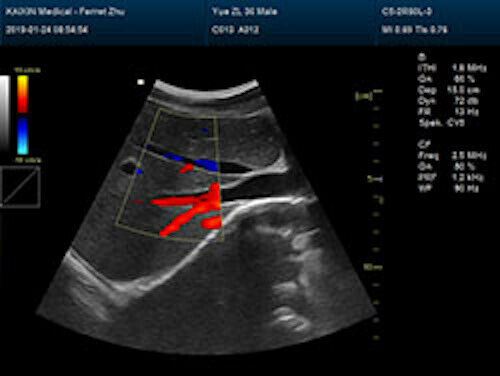

| Rich clinical application function • B+CF (Dual Images) • B+CF/PDI/DPDI+PW (Triplex) • Convex extended imaging technology • Linear array deflection/Trapezoidal imaging technology • Spatial compound Imaging technology • Panoramic imaging technology (optional) • 3D/4D imaging technology (optional) • Speckle noise removal technology • Pulse inversion tissue harmonic imaging technology (iTHI) |